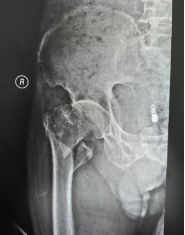

案例2:患者,88岁高龄,因摔伤致右髋关节疼痛伴活动受限3小时入院。入院诊断:右股骨粗隆间粉碎性骨折、重度骨质疏松。鉴于高龄骨质疏松粉碎性骨折对髓内钉力线与螺旋刀片锚定的严苛要求,科室以3D打印1:1骨折模型提供“实体沙盘”,助力医生反复进行骨折复位演练,精确测量进针点、主钉长度、前倾角及螺旋刀片深度精,评估复位稳定性,最后成功完成3D打印模型辅助下行粗隆间骨折PFNA闭合复位内固定术,保障了手术安全与效果。

(术前) (术后)